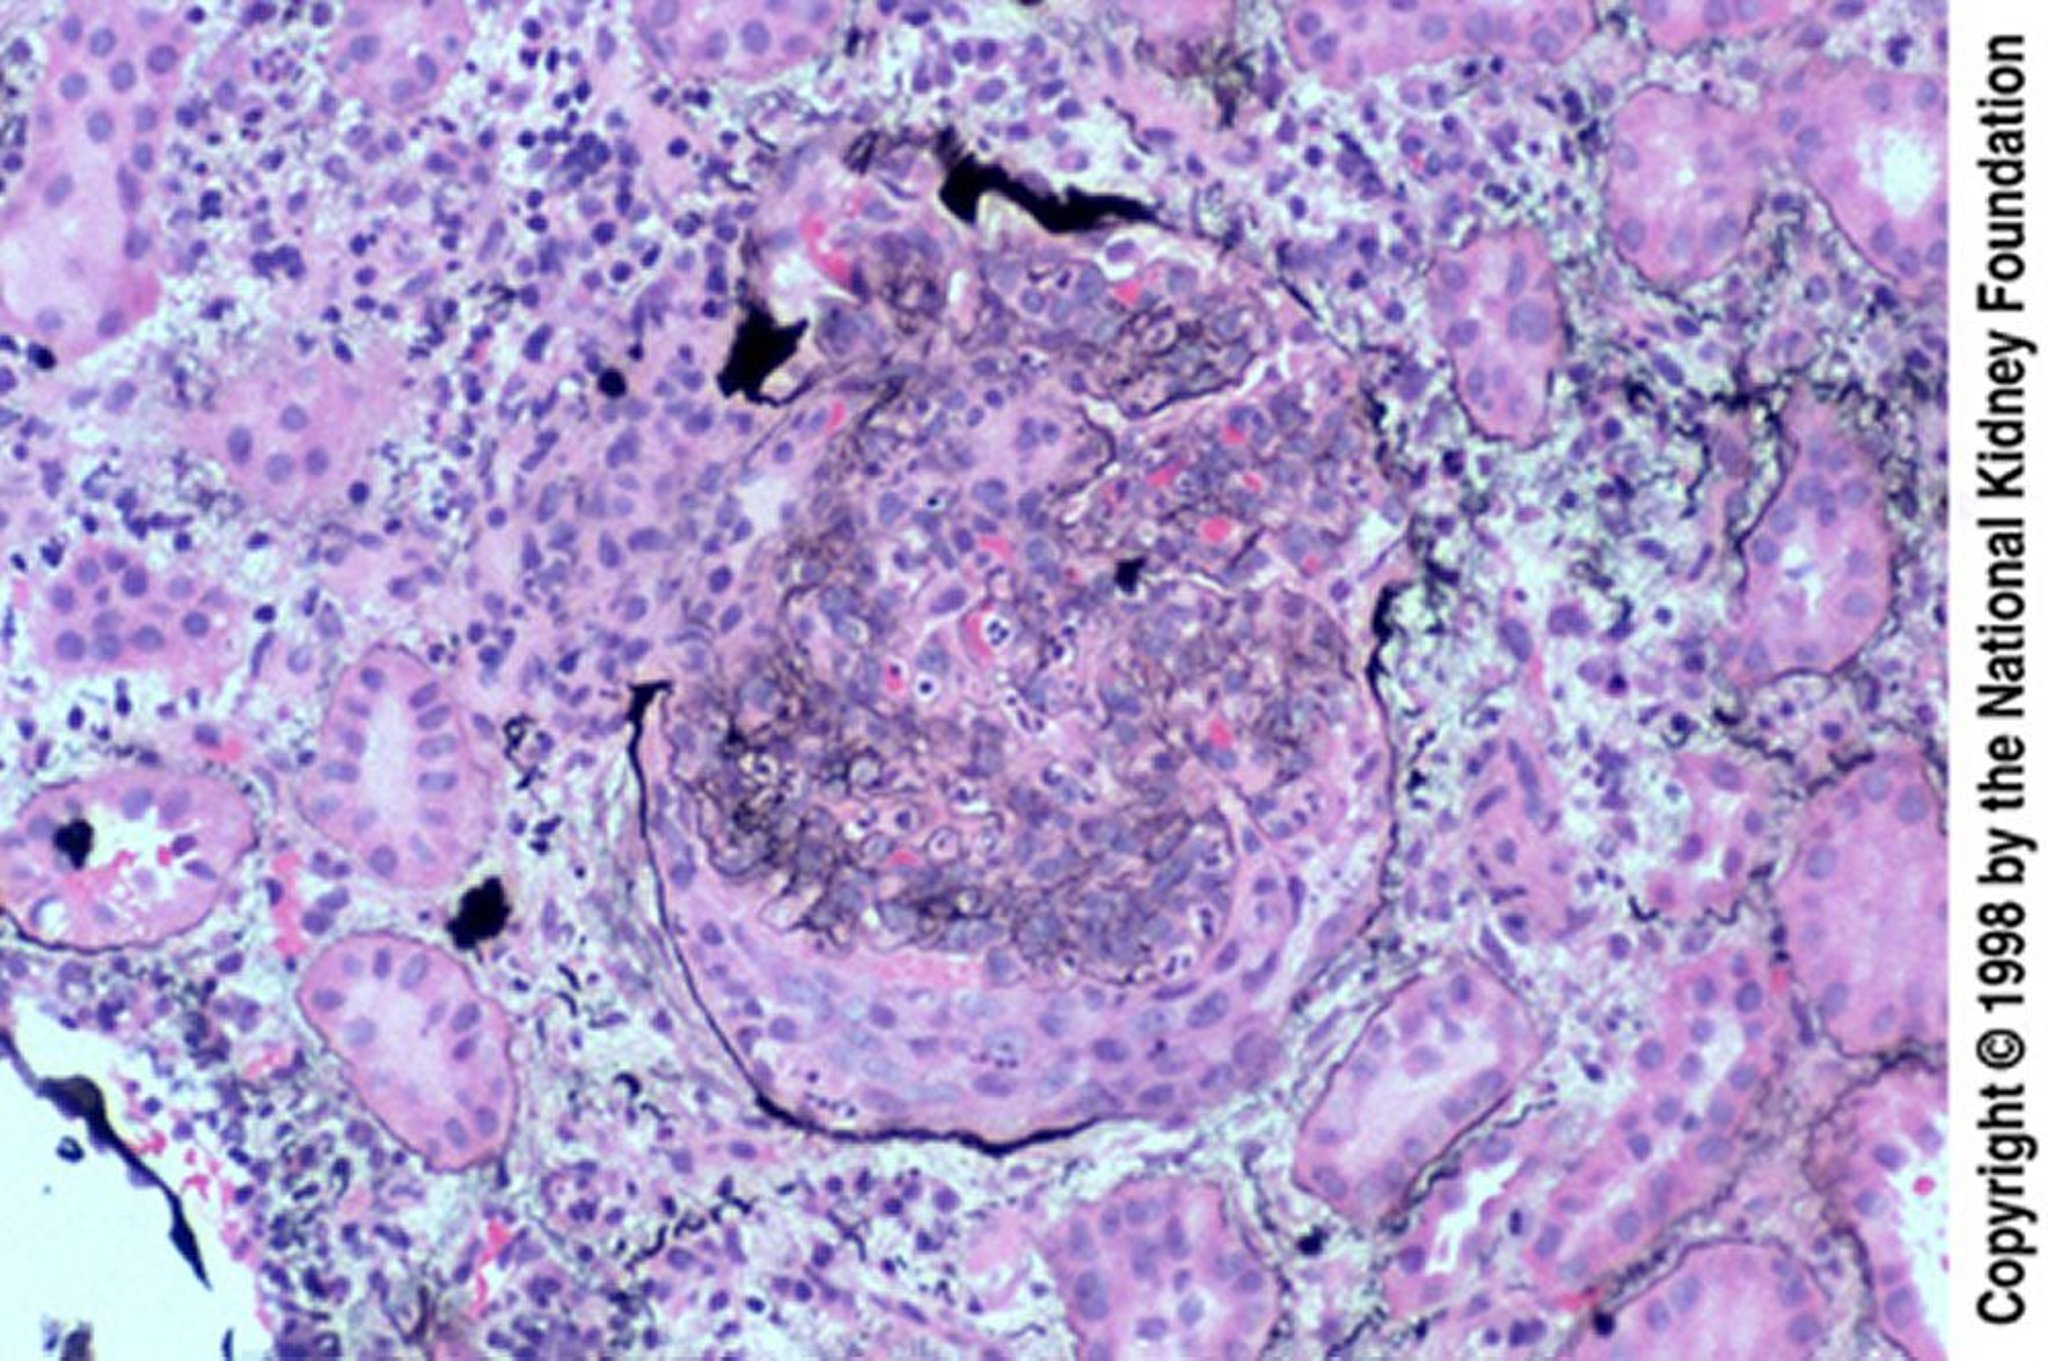

Glomerulonefrite pós-infecciosa (crescentes epiteliais)

Crescentes epiteliais são especialmente comuns quando a biópsia é tardia, após insucesso do tratamento. O crescente rompeu a cápsula de Bowman (coloração prata de Jones, × 200).

Image provided by Agnes Fogo, MD, and the American Journal of Kidney Diseases' Atlas of Renal Pathology (see www.ajkd.org).